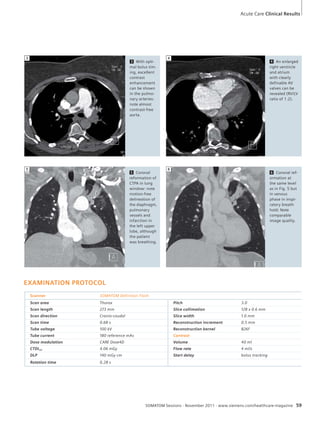

[1] Leng S, et al. Renal Stone Composition Differen-tiation

using Two Consecutive CT Scans and a

Non-Rigid Registration Algorithm (abstr). In:

Radiological Society of North America scientific

assembly and annual meeting program. Oak

Brook, Ill: Radiological Society of North America,

2011

1 Under development. Not available for sale in the U.S.

2 The information about this product is being provided for planning purposes. The product requires 510(k) review and is not commercially available in the U.S.

Science

iTRIM – a New Method for